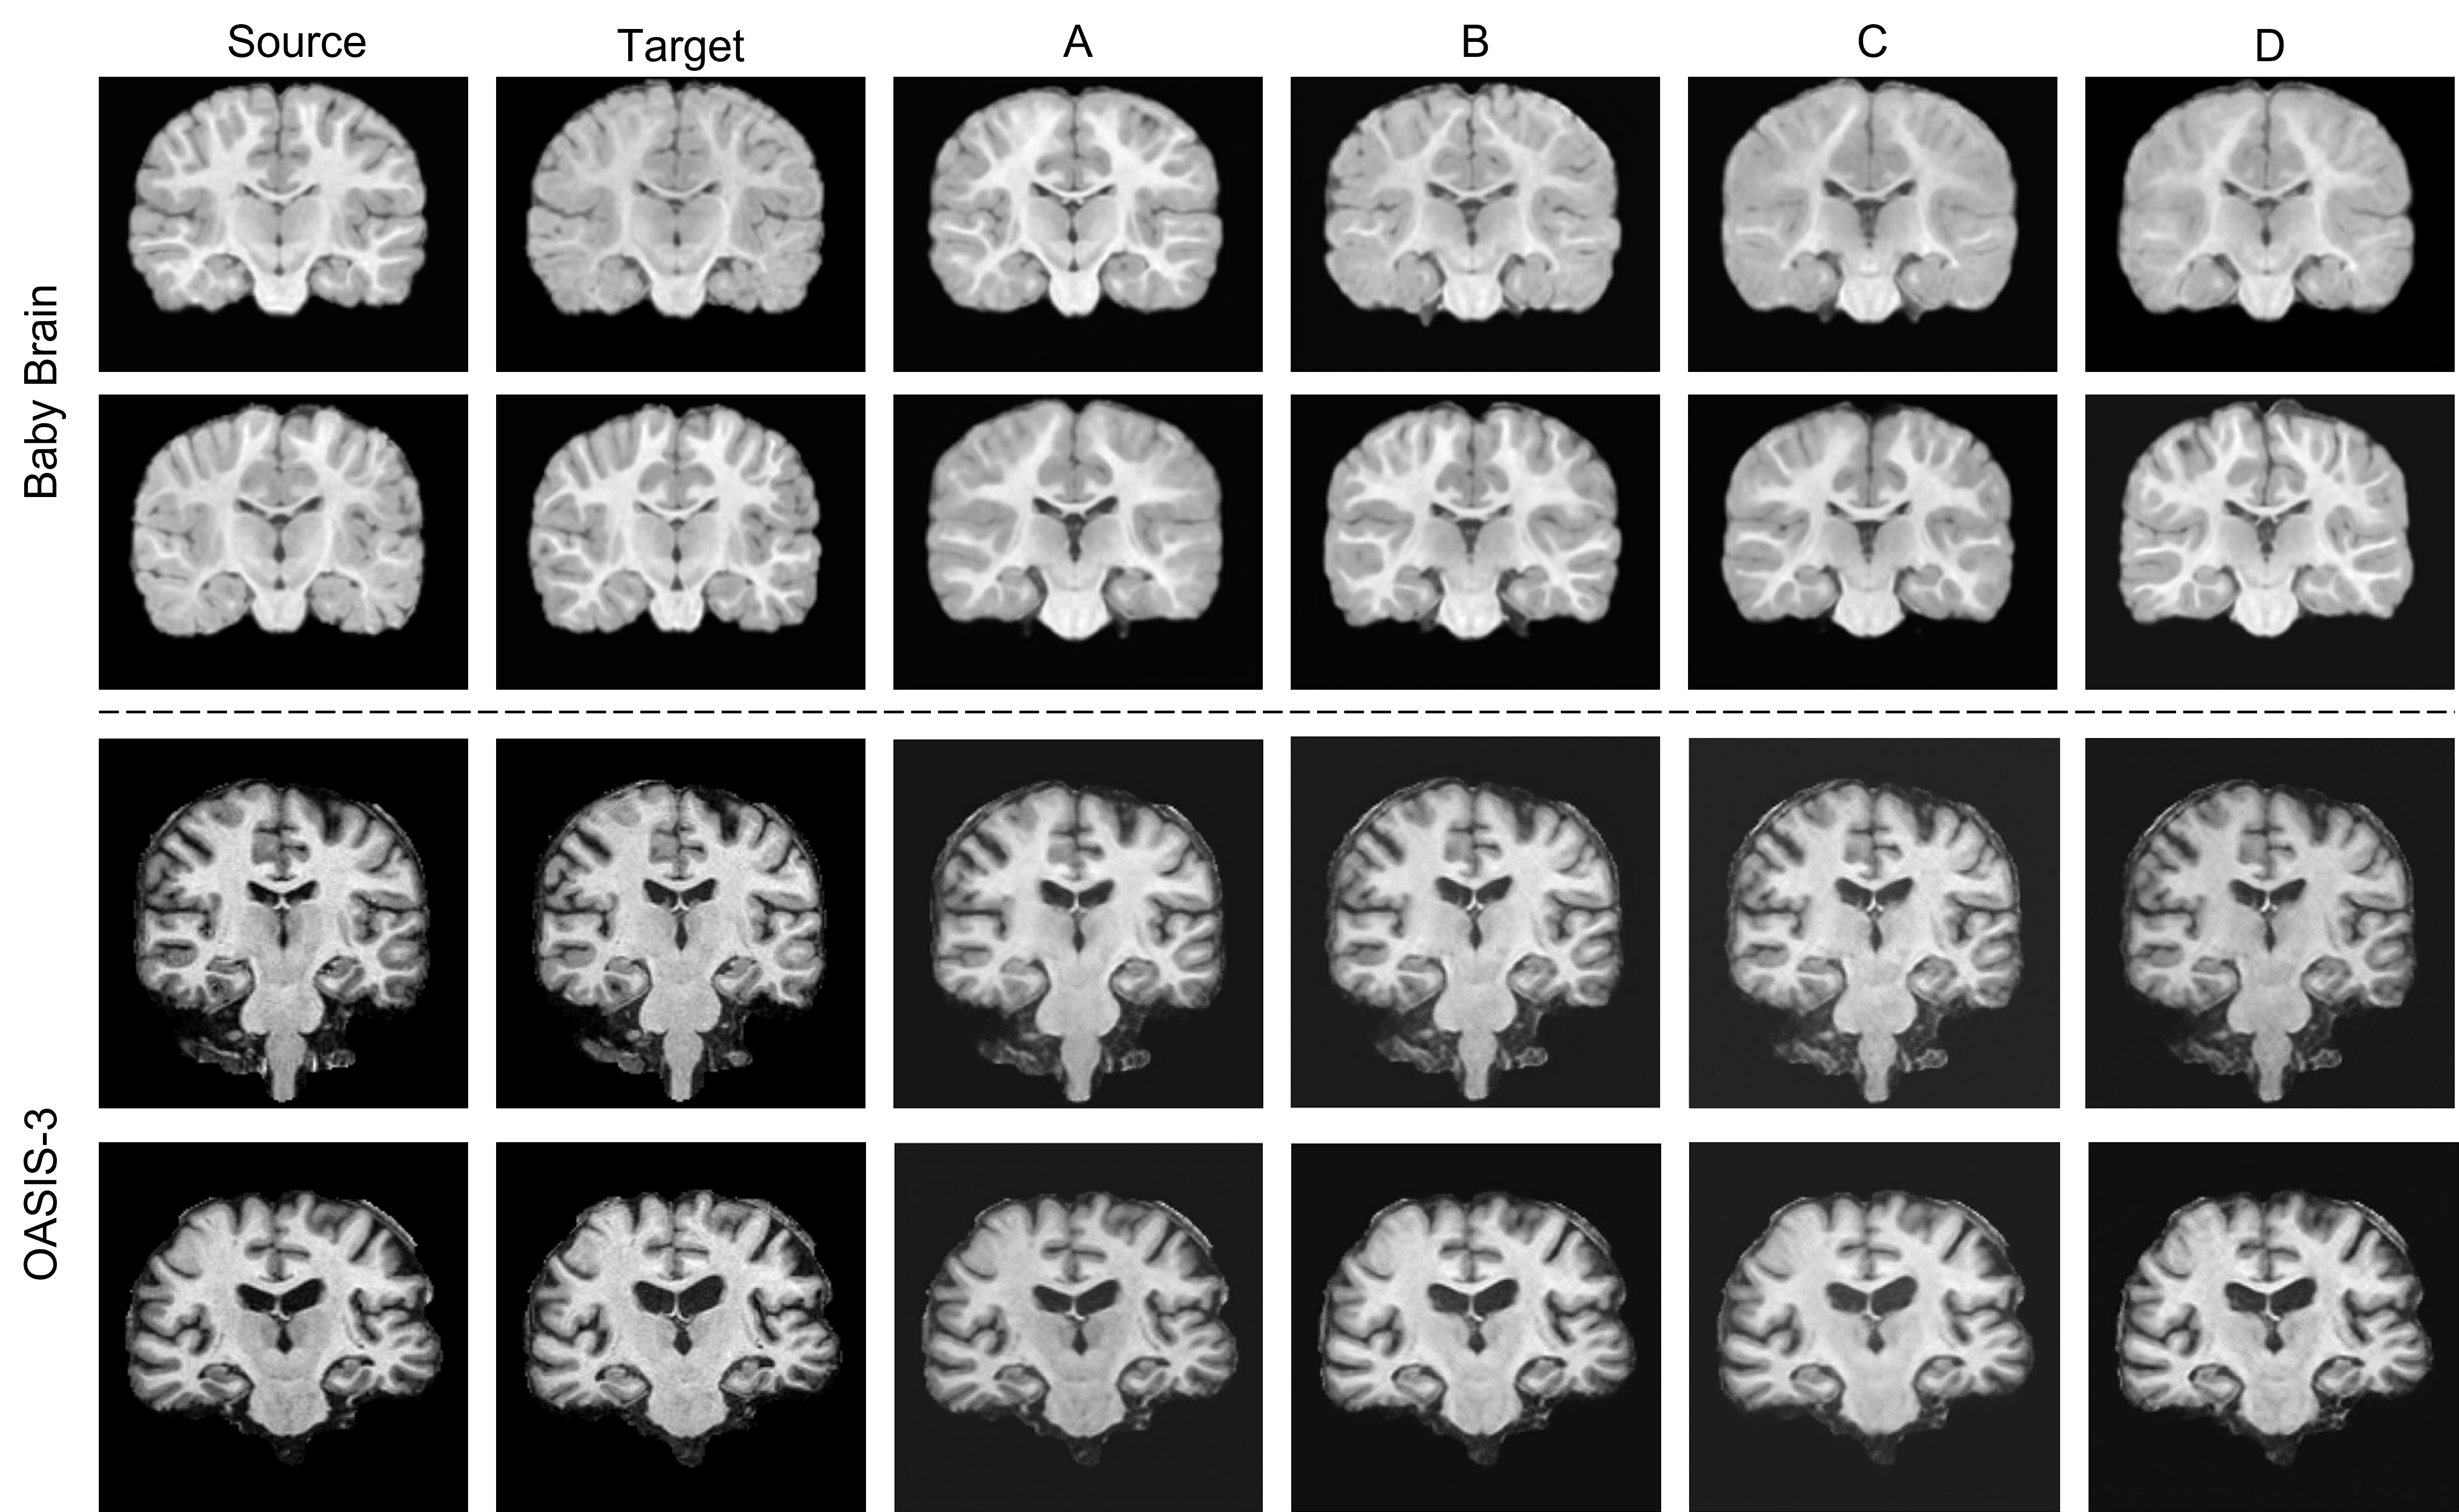

Refer to caption

Figure 2: Visualization of baseline comparison on the Baby Brain and OASIS-3 datasets. The brain images are generated by different models based on the source images, which are expected to align with the target images. In the first row, the source and target are similar in age, resulting in subtle yet discernible longitudinal changes. Our method preserves the identity more effectively compared to other non-identity-preserving baselines.

Tab. 1 presents a performance comparison of IP-LDM against SOTA methods on the OASIS-3 and Baby Brain datasets. On the OASIS-3 dataset, IP-LDM achieves the highest SSIM 0.949 and PSNR 35.15, indicating superior structural similarity and image fidelity. Additionally, IP-LDM records the lowest FID 4.733 and RMSE 1.868, reflecting high-quality and accurate image generation. The highest ARI 0.99 further underscores IP-LDM’s capability in maintaining identity preservation. Similarly, on the IBIS dataset, IP-LDM outperforms other methods with the highest SSIM 0.674 and PSNR 32.989, and the lowest FID 4.984 and RMSE 8.996, demonstrating its robustness in producing realistic and precise brain images during age transformation. Notably, the GAN-based method (cGAN) performs better on the Baby Brain dataset compared to the OASIS-3 dataset. We attribute this difference to the inherent characteristics of the datasets. Please refer to App. D for further details.

The visualization shown in Fig. 2 further underscores the superior performance of IP-LDM. The figure displays brain images generated by different methods across the Baby Brain and OASIS-3 datasets, generating target images based on source images. For both datasets, IP-LDM produces images that closely resemble the target images, maintaining fine structural details and anatomical accuracy. The generated images exhibit clear ventricles and well-preserved brain structures, indicative of successful identity preservation and realistic aging transformation. In contrast, images generated by cGAN and DAE display noticeable artifacts and structural inconsistencies. cGAN, while producing visually realistic images, often fails to maintain finer identity-specific details, leading to less accurate age transformations. DAE struggles with both realism and structural integrity, showing blurred and less detailed images. InstructPix2Pix performs better than cGAN and DAE but still falls short of the accuracy and fidelity demonstrated by IP-LDM, especially in maintaining subtle geometric variations and anatomical features.